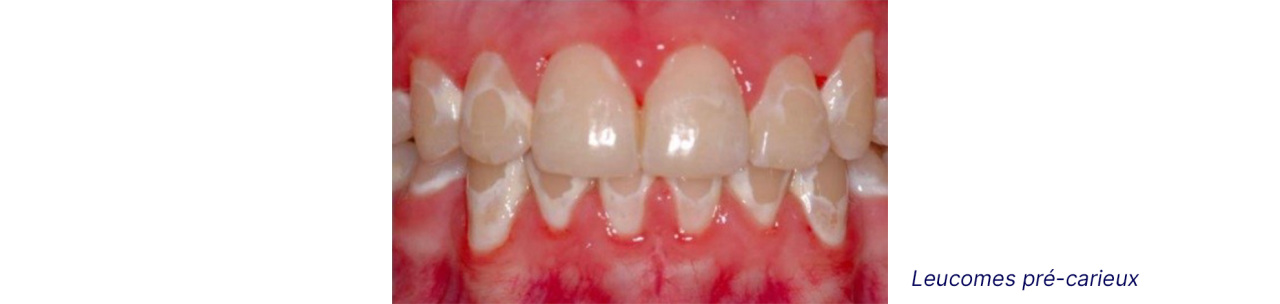

Les leucomes précarieux (white spot)

Dans le cas d’un brossage insuffisant, sur une longue période, un dépôt de plaque dentaire autour des bagues et à la limite de la gencive peut entrainer un début de déminéralisation de l’émail se traduisant par une marque blanchâtre (leucome pré-carieux). Dans un premier temps, cette marque est réversible à l’aide de traitements fluorés, mais est irréversible à un stade avancé. Le stade suivant étant une carie, il est parfois préférable de retirer l’appareil alors que le traitement n’est pas terminé.

Ensemble de deux images qui illustrent le risque de leucomes.